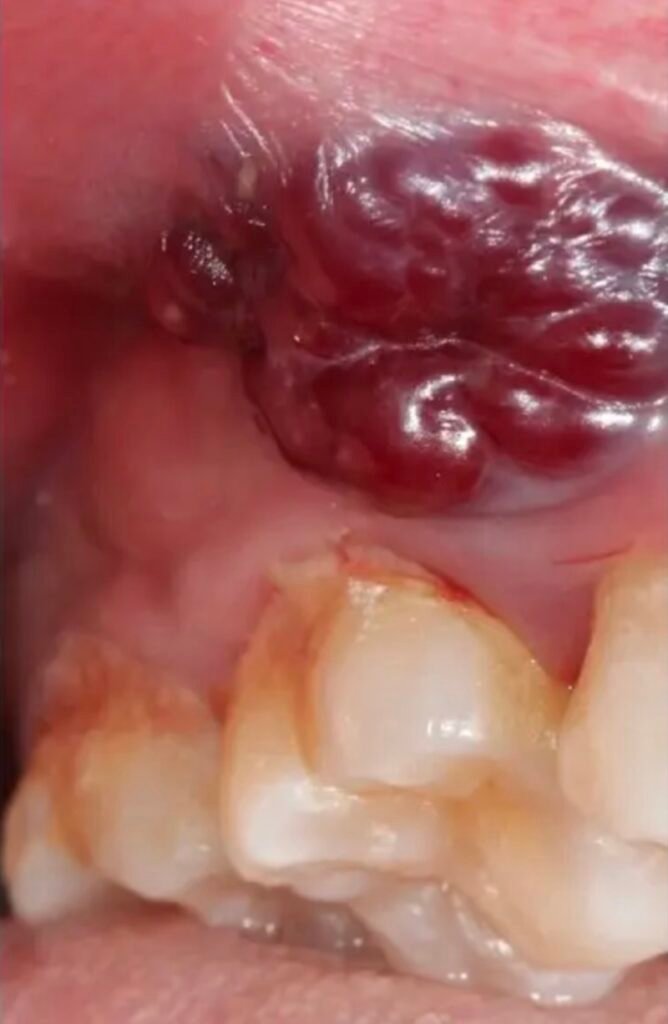

- Bultos, quistes o masas en la boca

Cirugía de quistes y tumores benignos

Tratamientos de lesiones en encías, lengua y paladar